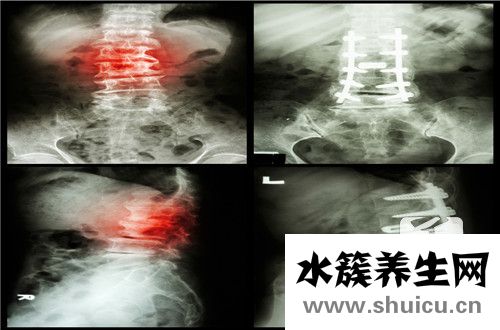

頸椎有許多功能可以控制我們整個上半身。我們所有的彎腰、起身和坐姿動作都是由脊柱和頸椎維持的。當脊柱嚴重時,會使患者感到背痛,甚至變形和突出。找到治療這種情況的方法至關重要。...

一般來說,頸部是最常用的部位。加上人們使用手機的時間增加,長時間彎腰會導致頸椎病有些人因為脖子疼,按脖子的時候會覺得脖子上有個腫塊。有些人害怕淋巴結,事實上,頸部很可能是甲狀腺腫的前期...